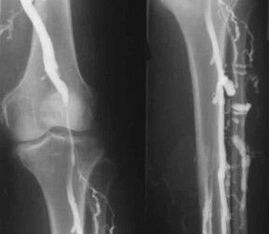

The most common instrumental diagnostic method is to use ultrasound examination of the venous vessels of the legs.This technique allows you to visualize the vascular system and determine the degree of progress of the pathological process.

- Phlebography.

- Photoplethysmography.

The use of venous occlusion allows determining the volume of blood in the veins of the lower extremities.